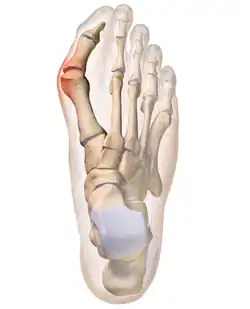

A bunion, also known as hallux valgus, is a deformity of the MTP joint connecting the big toe to the foot.[2] The metatarsal bone deviates from its normal straight-ahead position, and the head of the bone bulges out. The big toe often bends inward toward the other toes, and the joint becomes red and painful.[2] The onset of bunions is typically gradual.[2] Complications may include bursitis or arthritis.[2]

The bump itself is partly due to the swollen bursal sac or an osseous (bony) anomaly on the metatarsophalangeal joint. The larger part of the bump is a normal part of the head of the first metatarsal bone that has tilted sideways to stick out at its distal (far) end (metatarsus primus varus).

Bunions are commonly associated with a deviated position of the big toe toward the second toe, and the deviation in the angle between the first and second metatarsal bones of the foot. The small sesamoid bones found beneath the first metatarsal (which help the flexor tendon bend the big toe downwards) may also become deviated over time as the first metatarsal bone drifts away from its normal position. Osteoarthritis of the first metatarsophalangeal joint, diminished or altered range of motion, and discomfort with pressure applied to the bump or with motion of the joint, may all accompany bunion development. Atop of the first metatarsal head either medially or dorso-medially, there can also arise a bursa that when inflamed (bursitis), can be the most painful aspect of the process.